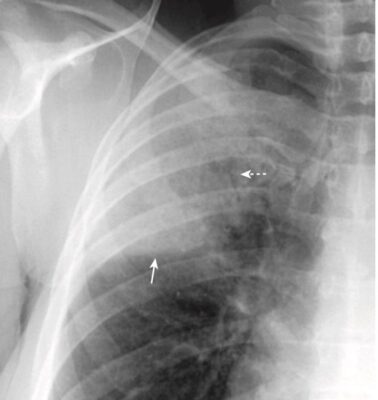

- Bệnh khoang chứa khí có thể biểu hiện dấu bóng bờ (dấu xoá bờ – silhouette sign) (Hình 4).

- Dấu xoá bờ xảy ra khi hai cấu trúc có cùng mật độ X quang (chẳng hạn như nước và mô mềm) chạm vào nhau sao cho rìa hoặc bờ giữa chúng biến mất. Không thể nói cấu trúc này này bắt đầu ở đâu và cấu trúc kia kết thúc ở đâu. Dấu hiệu bóng bờ không chỉ có giá trị ở ngực mà còn hỗ trợ cho việc phân tích các nghiên cứu hình ảnh ở những vị trí khác.